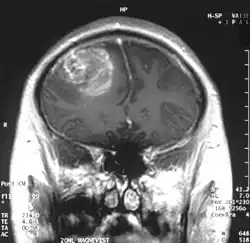

| MRI scan showing a glioblastoma with contrast enhancement | |

- Gliomas: Tumors arising from glial cells, which support and protect neurons. Subtypes are astrocytomas (from astrocytes), oligodendrogliomas (from oligodendrocytes), and glioblastomas (thought to derive from astrocytes).[2]

Magnetic resonance imaging (MRI) with contrast is the primary imaging modality for diagnosing brain and spinal cord tumors due to its high-resolution visualization of soft tissues. MRI helps identify the tumor's location, size, and potential impact on surrounding structures. In emergency situations or when MRI is contraindicated, a CT scan can be used as an alternative.[12]

Gliomas are the most common malignant brain tumor accounting for approximately 81% of malignant brain tumors and 26% of all brain tumors[16] They are the most common brain tumor in children up to 14 years (25.7%), the next most commonly found are pilocytic astrocytomas (17.5%), and embryonal tumors (15.7%).[16] The overall incidence rate of brain tumors in children is 6.2 per 100,000.[10] Glioblastomas are the most aggressive malignant glioma and make up approximately 47.7% of all gliomas, and are more commonly found in males.[10][16] Their incidence rate is 3.23 per 100,000 people.[10] The 5-year survival rate for glioblastoma is only 6.8%.[10]